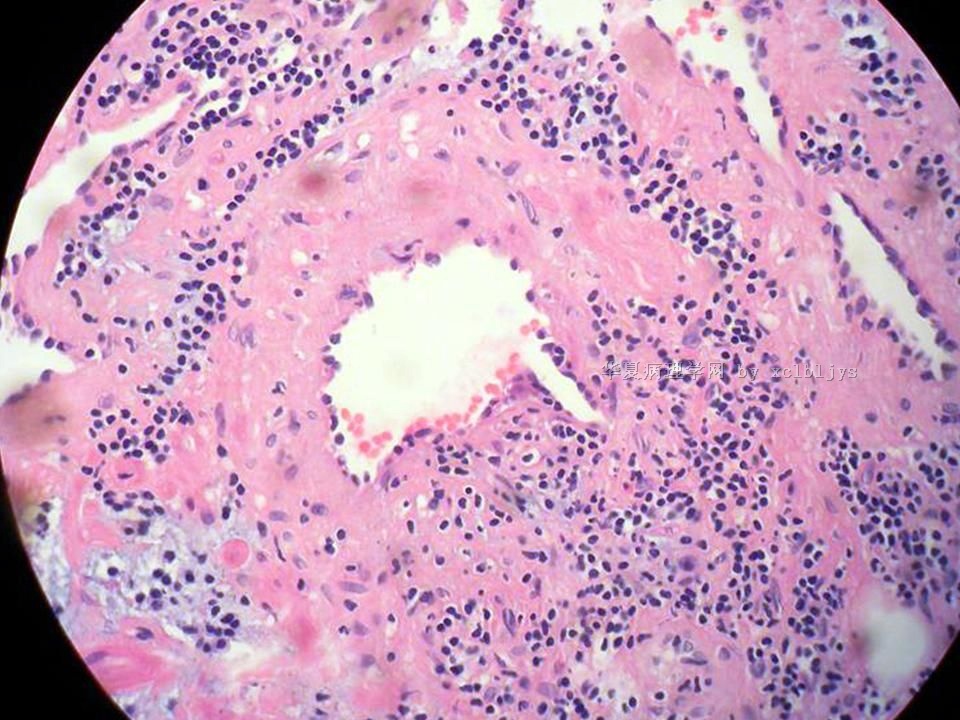

| 以下是引用xclbljys在2010-12-22 17:20:00的发言: 本例我们科室医生有两种意见:一种是炎性假瘤;第二种意见是炎性假瘤伴局限性Wegener肉芽肿。 依据是眼眶内肿块含有大量的动脉内膜炎改变,浸润的炎细胞有淋巴细胞、浆细胞、嗜中性粒细胞和嗜酸细胞等,如图16所示,炎细胞已经浸润动脉壁全层,应符合坏死性小动脉炎,但尚不能确定动脉壁弹力纤维层的破坏。 请各位老师点评! Wegener肉芽肿多发生在上呼吸道、肺、肾脏和皮肤等器官与组织。坏死性血管炎需证实有纤维素样坏死。小动脉炎多在皮肤病变比较明显。本例的小动脉炎或许是炎症引起的继发性改变。需要完善病史,查血免疫指标,看有没有系统性疾病。如果没有系统性疾病,还是考虑慢性炎症继发小血管炎。

血管炎是正常营养/供给血管的炎症性病变,而不是增生血管的炎症。血管炎往往有明显的临床相应症状,如皮疹。典型的Wegerner肉芽肿病有三联症(上呼吸道、肺、肾脏病变)。血管炎不仅是有炎症细胞,同时有血管壁的变性、坏死(纤维素样), 内皮细胞的变质和增生,炎症细胞浸润(包括中性粒细胞、淋巴细胞、组织细胞、嗜酸性细胞、巨细胞等)。不同类型的血管炎累及的血管大小、炎症细胞的类型、有无肉芽肿改变都不相同。血管炎的病因可以是过敏、自身免疫、胶原性疾病、感染等多种因素。